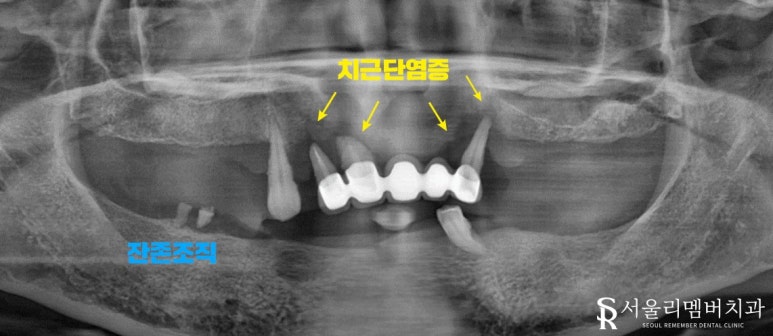

서울대입구역 치과 에서 실제 구강 내를 확인해 본 결과..

치아 상실은 물론이며 여기저기 염증과 치석, 치은 퇴축 등 관리가 잘되지 않았다는 걸 알 수 있었습니다.

어금니 쪽 구치부들은 2개의 약간의 잔존조직을 제외한 채 형태를 찾아볼 수 없었는데요.

그나마 남아있던 앞쪽 전치부도 상황은 같았습니다.

오래된 보철 안으로 충치, 염증, 치주 질환 등이 생겨 주위 잇몸에 물집이 잡히고 부종이 나타나있네요.

보아하니 환자께서 느끼셨을 통증 또한 컸을 것으로 짐작되었습니다.

편하게 식사하는 건 꿈도 못 꾸셨을듯한 구강이네요.

어쩌면 앞쪽 치아들은 살릴 수 있지 않을까? 하며 자세히 살펴보았는데요.

아이고.. 이미 잇몸이 내려앉아 뿌리 부근에 염증이 진행되고 있었습니다.

곧 덜렁덜렁 흔들리고 자연스레 빠져버리게 되겠군요.

아무래도 전체적인 치료가 필요할 것 같습니다.